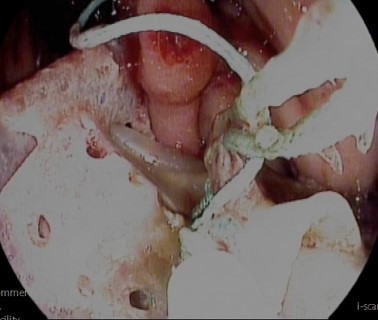

An urgent gastroscopy is performed, revealing a food bolus which is fragmented and removed, exposing friable mucosa with oozing bleeding, decubitus ulcers, and a suture thread over a whitish area compatible with surgical mesh (Figure 1). Due to suspicion of pressure-induced perforation and risk of iatrogenic injury, the exploration is suspended without advancing into the gastric cavity.

Figure 1. Whitish, firm material with exposed suture thread following food bolus disimpaction, compatible with surgical mesh.

Figure 1